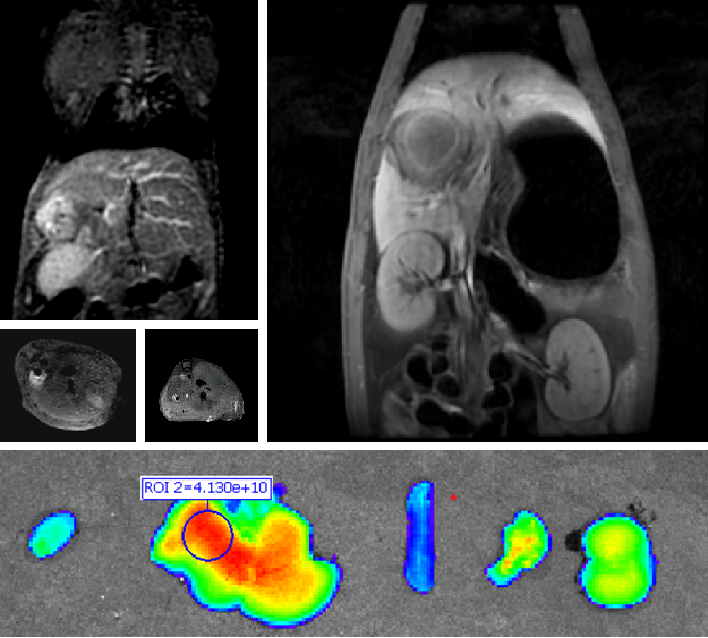

双模态造影剂PL002

PL002是浙江普利药业有限公司研发的荧光/磁共振双模态造影剂,开发荧光/磁共振双模态造影剂成为提高原发性肝癌手术效率的有效方案。双模态造影剂的荧光成像能力可用于肝癌术中荧光导航,而磁共振增强能力可用于在术前判断肝脏代谢能力,推测肿瘤及肝脏对造影剂的摄取情况,提高肿瘤诊断精度,降低术前规划难度。

PL002相较于吲哚菁绿具有明显优势。目前吲哚菁绿在临床使用中存在给药到手术时间不确定的问题,可能造成病灶与正常组织对比度不足,影响术中的病灶的判断,PL002采用独特的钆络合物与荧光分子共价键结合的分子结构设计,这种设计能够让医生在术前通过磁共振成像确定造影剂在病灶中的聚集情况,进而针对患者个体情况来对手术时间进行规划。同时,由于PL002体内更为稳定,在荷瘤小鼠模型中同等条件下荧光成像效果维持时间长于现有荧光造影剂,也保证了其在临床应用中具有更宽的手术窗口。